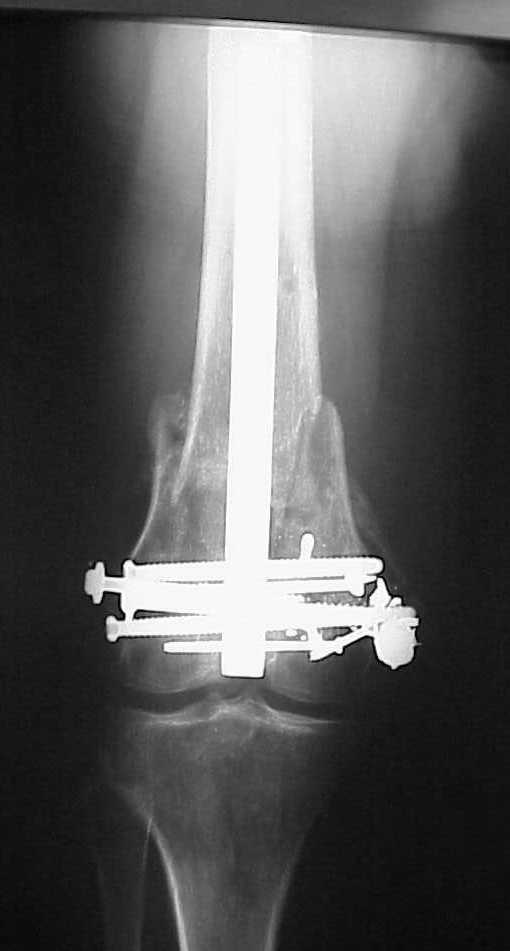

Да, примерно так и сделали. Надо было, пожалуй, кончик гвоздя еще спилить, чтобы отверстие было еще дистальнее. Англоязычные коллеги еще

советовали винты в передне-заднем направлении вводить, но что-то не увидел, где там подходящее место.

Since it was done closed the shaft will heal or at worst need an exchange IMN.

Nice job.

Мы пошли на операцию с планом попытаться сделать закрытый интрамедулярный, а не получится - сделать аппаратом. Посчитали, что получилось, хотя на еженедельной конференции ожидаются некоторые проблемы с объяснениями ;-)

Насчет стабильности для ранней нагрузки, конечно, сомнительно, но при таком повреждении ранняя нагрузка противопоказана в любом случае. Для ранних движений Должно хватить. Снимки в следующем сообщении.